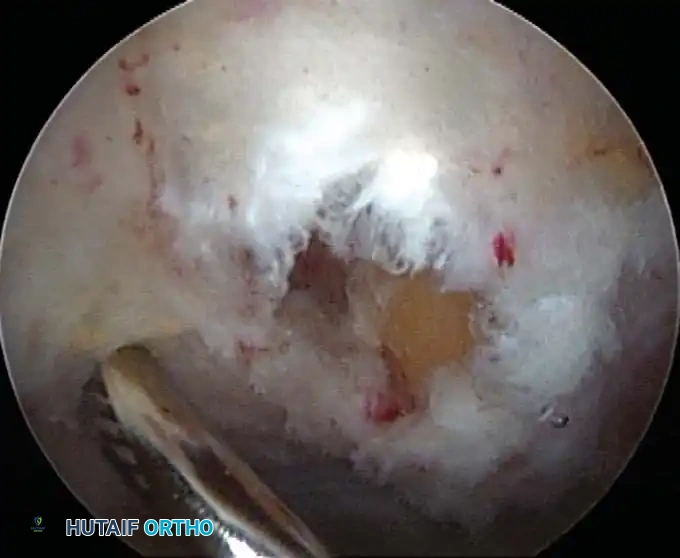

Electrocautery and Radiofrequency Ablation

In addition to hydrostatic pressure, active hemostasis is achieved using arthroscopic electrocautery or bipolar radiofrequency (RF) ablation devices. These wands are indispensable for coagulating bleeding vessels in the subacromial bursa, releasing the coracoacromial ligament, and meticulously preparing the footprint for rotator cuff repair without obscuring the visual field with hemorrhage.

Furthermore, the addition of epinephrine (typically 1 mg per 3 liters of irrigation fluid) induces local vasoconstriction, significantly reducing capillary oozing. When combined with controlled hypotensive anesthesia (maintaining mean arterial pressure between 70-80 mm Hg), the surgeon is afforded a pristine, bloodless field, allowing for the precise execution of complex knot-tying and tissue mobilization.